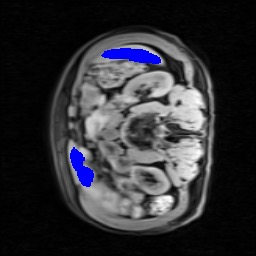

Transformers have made remarkable progress towards modeling long-range dependencies within the medical image analysis domain. However, current transformer-based models suffer from several disadvantages: (1) existing methods fail to capture the important features of the images due to the naive tokenization scheme; (2) the models suffer from information loss because they only consider single-scale feature representations; and (3) the segmentation label maps generated by the models are not accurate enough without considering rich semantic contexts and anatomical textures. In this work, we present CASTformer, a novel type of generative adversarial transformers, for 2D medical image segmentation. First, we take advantage of the pyramid structure to construct multi-scale representations and handle multi-scale variations. We then design a novel class-aware transformer module to better learn the discriminative regions of objects with semantic structures. Lastly, we utilize an adversarial training strategy that boosts segmentation accuracy and correspondingly allows a transformer-based discriminator to capture high-level semantically correlated contents and low-level anatomical features. Our experiments demonstrate that CASTformer dramatically outperforms previous state-of-the-art transformer-based approaches on three benchmarks, obtaining 2.54%-5.88% absolute improvements in Dice over previous models. Further qualitative experiments provide a more detailed picture of the model's inner workings, shed light on the challenges in improved transparency, and demonstrate that transfer learning can greatly improve performance and reduce the size of medical image datasets in training, making CASTformer a strong starting point for downstream medical image analysis tasks.